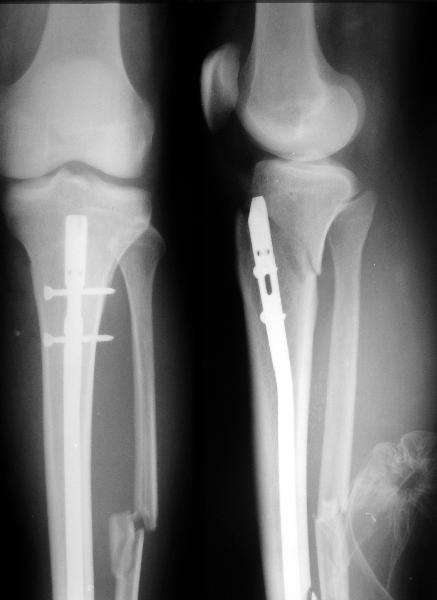

45 y/o male sustained in MVA 3 months ago. Had closed proximal third left tibial fracture. Initially treated in rural hospital where IM nailing was attempted but complicated with longitudinal tivial split down to tibial shaft to distal tibial metaphysis. Nailing was abandoned and cast was applied and patient was reffered to us.

We applied Ilizarov frame, which was performing nice until 1 month ago when patient started to bear full weight. Yesterday patient presented to us. Gross Ilizarov frame instability and fracture movement was detected. Patient has minor pain in FWB, pins are infection free.

My plan was to remove frame, apply cast for 2 weeks and then perform closed reamed locked nailing following 6 months PWB and then gradual FWB.

IMHO this fracture could be nailed. And reaming will act as internal osteoplasty. If I get axis straight and use distal locking first and performe backstroke technique I will get reasonable contact and some compression at the fracturesitee.